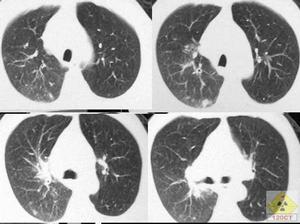

1.X線檢查大多有明確的肺實質性改變,可見肺紋理增加,片狀陰影,粟粒狀改變,肺門陰影增大等。早期兩肺紋

理增強,繼而兩肺出現散在性點狀浸潤,邊緣模糊,以中下部肺野為多。隨著病情發展,肺部陰影趨於緻密,並有互相融合的傾向,形似支氣管肺炎。當蟲卵死亡,周圍組織反應消失,病變逐漸吸收縮小,邊緣轉為清晰整齊,遺留點狀陰影,與粟粒狀肺結核的表現近似,以後點狀陰影逐漸減少,有時可見鈣化現象。典型X線病變一般在3~6個月內逐漸消失。少數病例肺小動脈廣泛閉塞可引起肺動脈高壓及右心肥厚表現。如有多次疫水接觸史而反覆感染,肺野可有新舊不一,密度不等且大小不均的粟粒狀陰影。慢性肺血吸蟲病可表現有密度增高的片狀陰影,與健康肺組織有明確邊界,狀如炎性假瘤或腫瘤